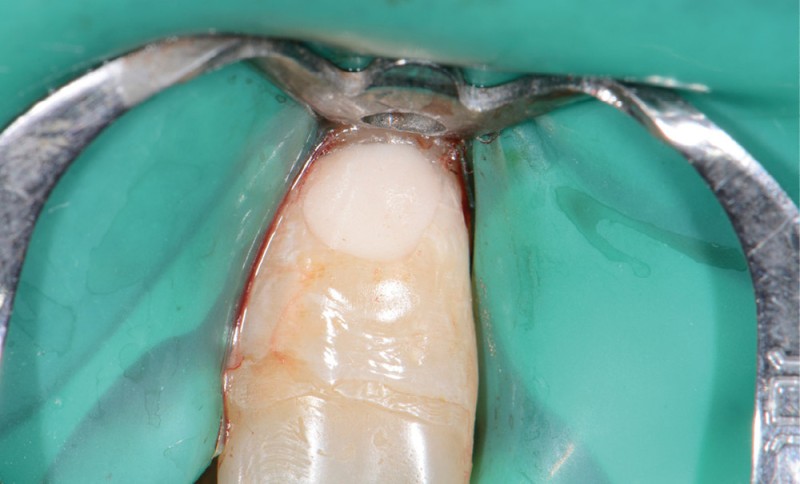

Perforation infra-osseuse avec accès visuel direct (fig. 3)

Ce type de perforation est également la plupart du temps iatrogénique et survient lors de la recherche ou de la mise en forme canalaire, lors de la préparation pour un logement de tenon radiculaire. Situées au niveau du plancher pulpaire des dents pluriradiculées, ou au niveau des entrées canalaires des dents monoradiculées ou pluriradiculées, il s’agit le plus souvent de perforations à quatre parois. Si la perforation survient en cours de traitement, elle doit être gérée immédiatement pour un meilleur pronostic (fig. 4). Néanmoins, il est important de prendre en compte l’épaisseur résiduelle du plancher. Si le plancher est trop fin, il ne sera pas possible d’envisager de traiter la perforation.

Protocole pour la gestion d’une perforation du plancher avec la technique du tunnel (cela n’est réalisable que si le plancher est présent en épaisseur suffisante, ce qui n’est pas nécessairement le cas lors de perforations iatrogènes) :